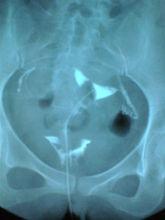

輸卵管照影

及時確診的方法多種多樣。輸卵管通氣試驗,輸卵管通水試驗,子宮輸卵管造影,子宮輸卵管超聲檢查,內鏡(腹腔鏡、宮腔鏡、輸卵管鏡),放射性核素子宮輸卵管造影等檢查,如果必要,還可以進行開腹探查,總之是可以及時明確診斷的。早期明確診斷,對控制病情繼續發展有一定的好處。